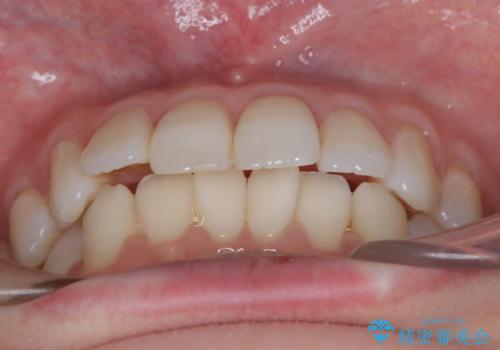

インビザラインモデレートによる前歯の叢生改善|IPR最小限で自然な歯並びへ

前歯の叢生は解消され、自然で調和の取れた歯並びが得られました。

「歯をほとんど削らずにきれいになった」と、患者様にもご満足いただけました。